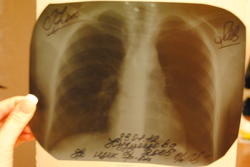

А вопрос-что за образование у ребенка 6 лет , на ренгеновском снимке кто-то что-то видит? Онколог вчера сказал о том,что тень уменшилась спустя месяц. Поставил тимомегалию и тимому под вопросом.

"Кто-то" "что-то" всегда видит. Только оценивают все по разному. На рентгене тень действительно уменьшилась - больше данных за тимомегалию. Но королева доказательств в данном случае - КТ. Думаю, что повторного КТ, а то и с контрастом - не избежать. Впрочем, в Герцена специалисты квалифицированные, разберутся.

Посмотрите,пожалуйста,отсканированные снимки....

Кристина.

Что это может быть?